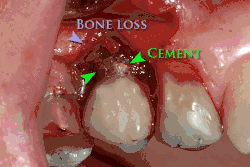

Осложнения имплантата

- тяжёлые формы заболеваний пародонта;

Особое значение имеет уровень гигиены полости рта. Имплантация не может быть выполнена без санации полости рта (все зубы должны быть вылечены), поскольку любой очаг инфекции в организме может свести на нет работу имплантолога из-за высокой вероятности последующего отторжения вживлённого имплантата.

Установка зубных имплантатов может вести к периимплантиту, который возникает из-за бактериальной флоры, попадающей на внешнюю поверхность имплантатов через зубной налет. Лечение данного заболевания проводили корейские исследователи с использованием титановой щетки.